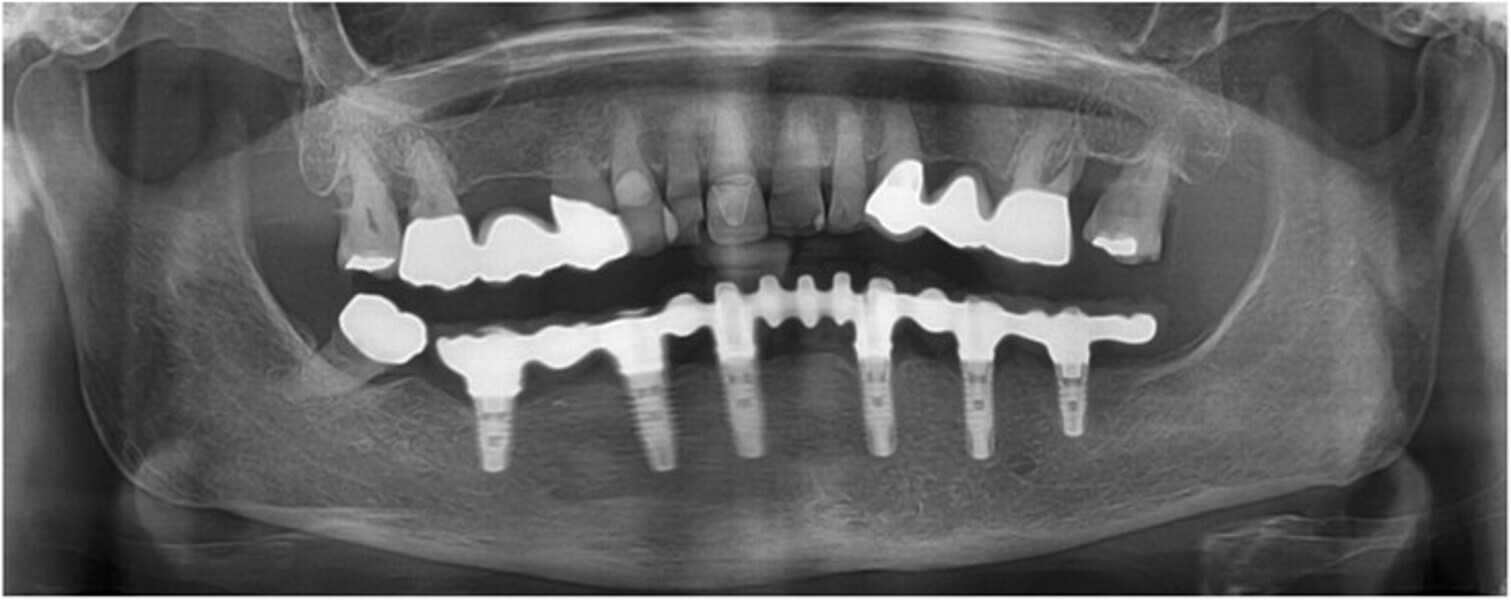

Fig. 10: Post-op panoramic radiograph.